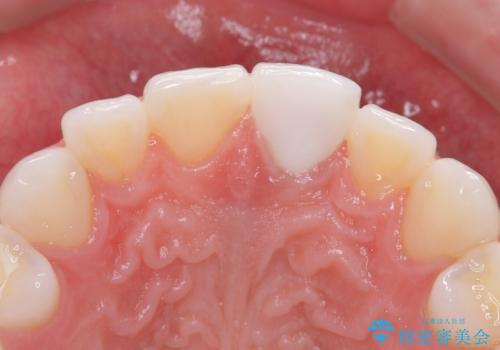

ぶつけて変色した前歯 オールセラミッククラウン治療

- 以前ぶつけて神経を取り除いてから、徐々に変色してきた前歯が気になるとのことで来院された患者様です。

神経を取り除いた歯の変色はホワイトニングでは十分に改善できないため、オールセラミッククラウンにて補綴治療を行うこととしました。

予想通り色と形の修正が多く必要となりましたが、最終的には納得のいく仕上がりとなりました。